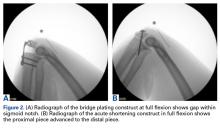

Figure 2.

After each fixation, radiographs were taken for measurement of maximum flexion and extension and amount of olecranon removed (Figures 2A, 2B). Gross stability to valgus and varus stress was examined under fluoroscopy after fixation, as it would be performed during surgery using manual valgus and varus load in full extension, 30° of flexion, and full extension in both supination and pronation. Any ulnohumeral joint line opening relative to baseline was considered a sign of instability.24